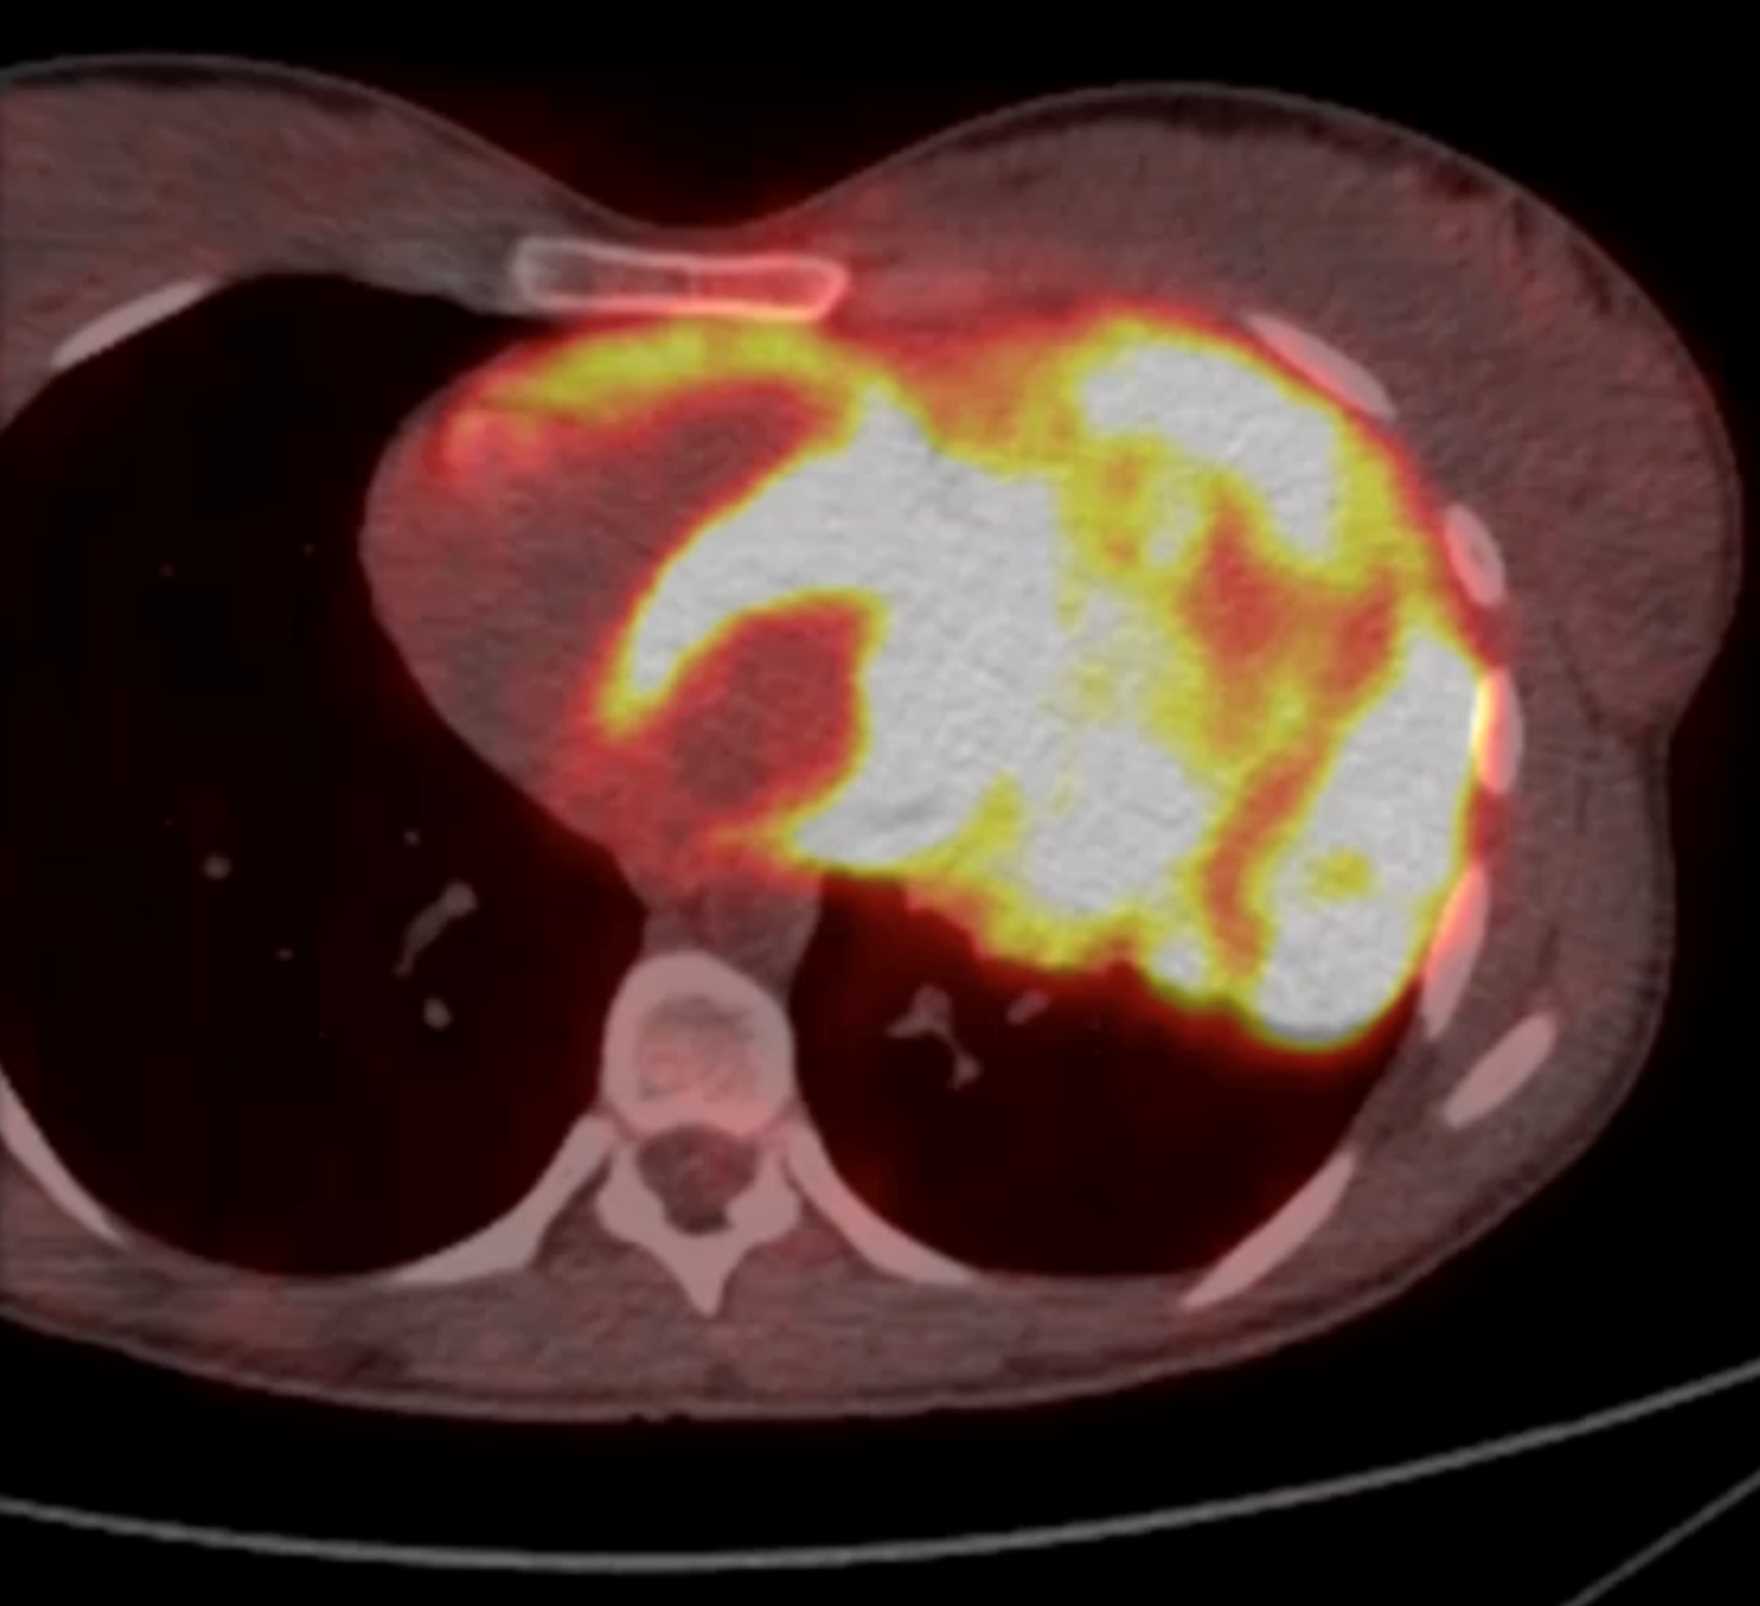

Subtle Adenocarcinoma Pancreas